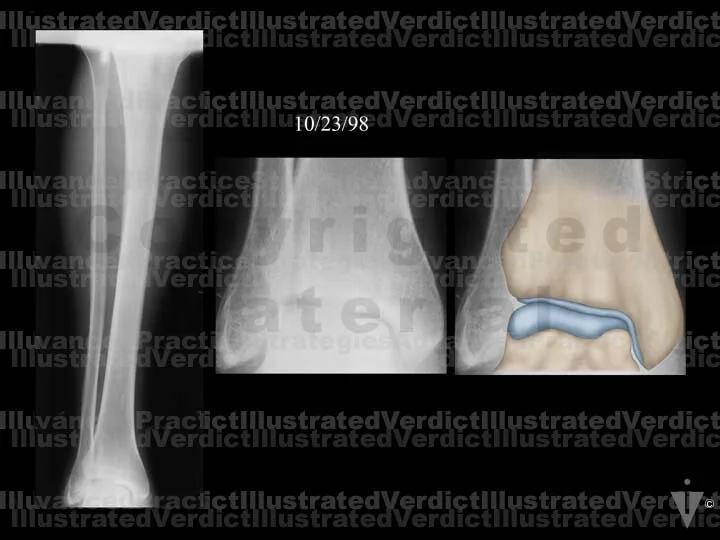

1. Original film

2. Original film with enhanced illustration